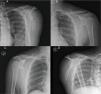

Se solicitaron radiografías de hombro y escápula bilaterales, en las cuales se observaron fracturas del cuerpo de la escápula izquierda con conminución, leve desplazamiento y angulación, además de fractura del cuerpo de la escápula derecha con desplazamiento sin angulación significativa (figs. 1–2). Por sospecha de contusión pulmonar se solicitó angiografía por tomografía Computada (angio-TC), la cual descartó alteraciones a nivel pulmonar, pero puso de manifiesto fracturas de los cuerpos vertebrales de T3 y T4 por acuñamiento con invasión del canal medular en T4, fracturas de las apófisis espinosas de T2 y T3, y fractura transversal no deprimida del cuerpo del esternón (figs. 3–5).